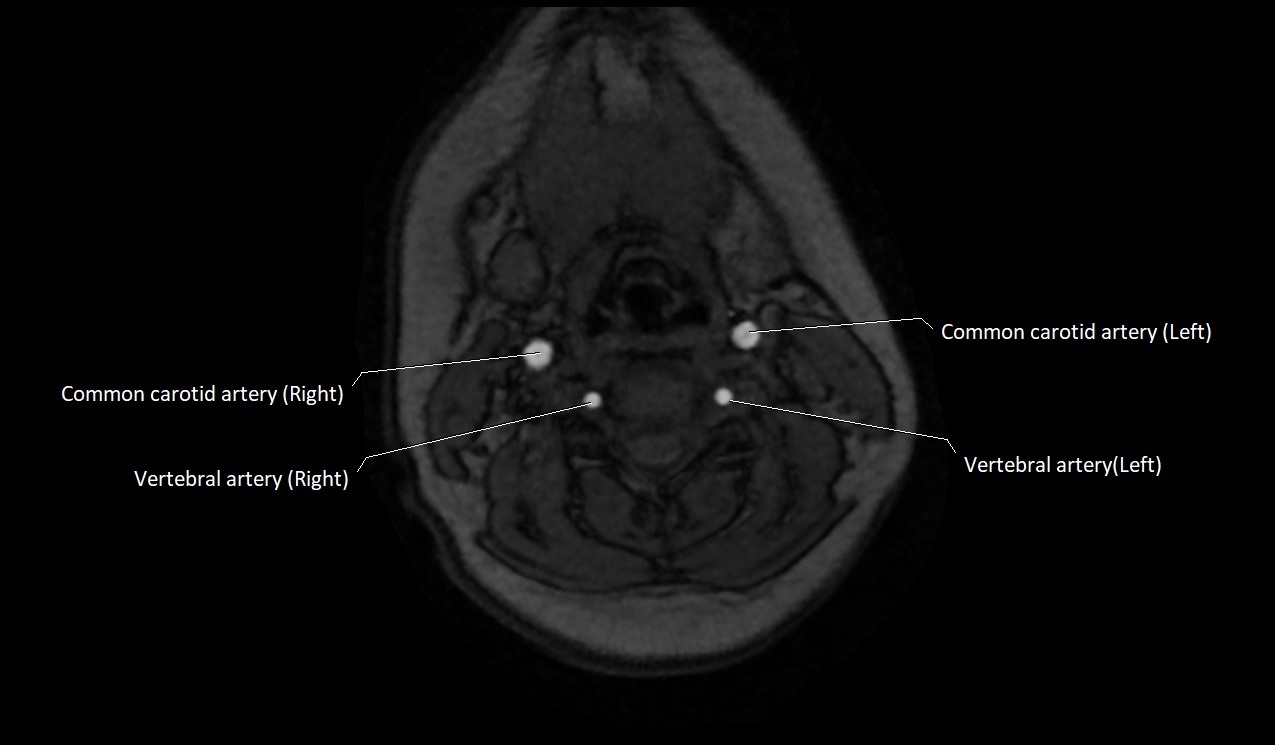

CT image

image